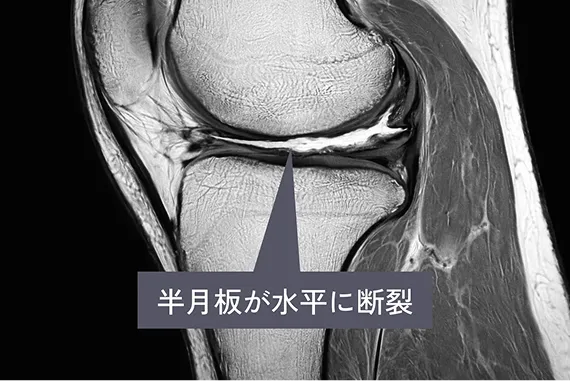

診断

半月板損傷かどうかを調べるには、膝の動きや痛みの出方を確認するいくつかの徒手検査があります。代表的なものとして、ApleyテストやMcMurrayテスト、膝を過伸展させるHyperextensionテストなどがあります。また、膝の押したときの痛み(圧痛)も診断の手がかりになります。

半月板はレントゲンでは見えないため、詳しく状態を確認するにはMRI検査が必要です。MRIを使うことで、損傷の形や範囲を正確に把握でき、適切な治療方法を決める際に非常に役立ちます。

MRI

半月板が水平に断裂している様子を示したMRI写真

長年膝の痛みがあり、ヒアルロン酸注射やPRP治療を受けても改善しない場合、軟骨や半月板の損傷が進行していることがあります。特に半月板が水平断裂していると、膝の曲げ伸ばしで損傷部分が挟まり、痛みで関節の動きが制限されます。